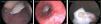

A su ingreso en planta, a las 24 h del inicio del cuadro clínico, dada la no mejoría de los síntomas con la administración del tratamiento médico, se realiza radiografía de tórax urgente. Se observa imagen de cuerpo extraño, de localización anterior a la aorta ascendente, en proyección lateral (fig. 1), sin evidenciar consolidación en la base pulmonar derecha (fig. 2). Se practica endoscopia digestiva alta, identificándose concha de bivalvo en esófago medio (fig. 3) con mucosa esofágica edematosa, eritematosa, con pequeña úlcera. Se extrae la concha con cesta de polipectomía, consiguiendo resolución de los síntomas.